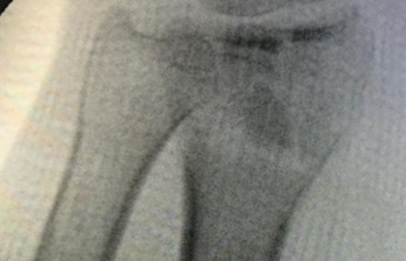

Los procedimientos más comunes en cirugía de la mano son aquellos destinados a reparar traumatismos, incluyendo lesiones de tendones, nervios, vasos sanguíneos, y articulaciones; huesos fracturados; y quemaduras, cortes, y otros daños de la piel.